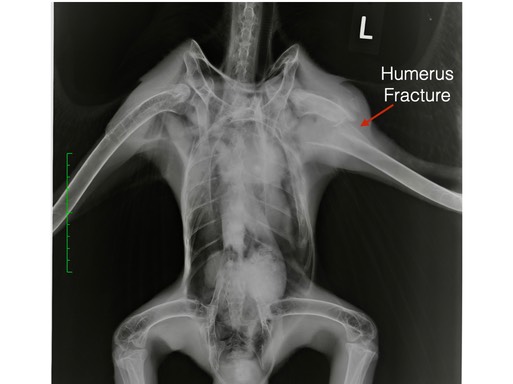

Bald Eagle 21-588

This young Bald Eagle was found on the ground near Moses Lake, WA. The land owner noticed there seemed to be a problem with one wing. Sadly, he was correct. The eagle’s left humerus was fractured. Even with surgery the likelihood of the eagle being able to fly well enough to be released was very poor. He was humanely euthanized.